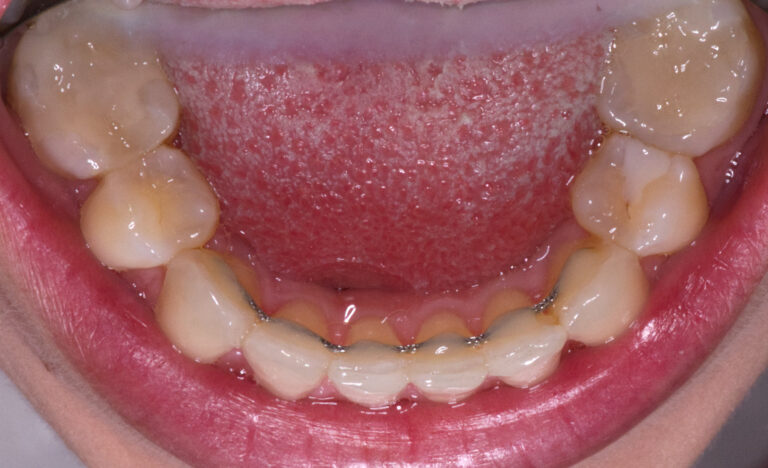

Kieferorthopädie, Zahnspange

5 Monate

Von Behandlungsbeginn bis Ende.

Vorher

Retainer unsichtbar verklebt, um das Behandlungsergebnis dauerhaft zu halten.